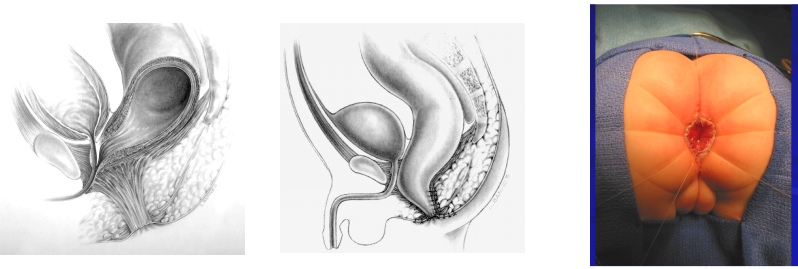

治 疗

目的:建立一个括约功能良好的肛门

▷ 高位及中位

- 结肠造瘘生后

- 6~12月 根治术

▷ 低位

- 后矢状入路肛门直肠成形术(PSARP)

- 女性 低位 扩肛术 6~8月肛门直肠成形术